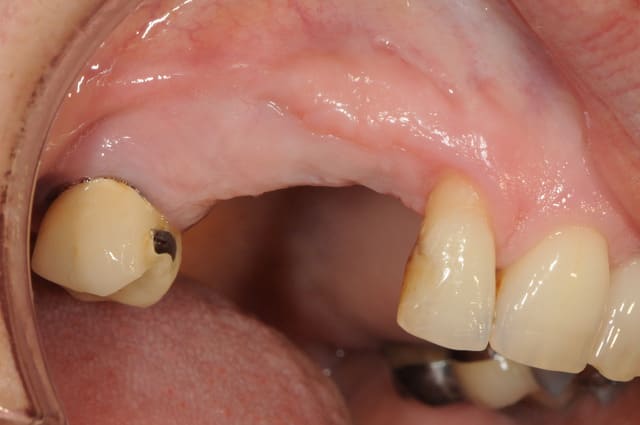

pose implants

cicatrisation gingivale

mise à jour et aménagement tissulaire type Palacci

modification des collets et des bords libres

prise empreinte

piliers

couronnes...